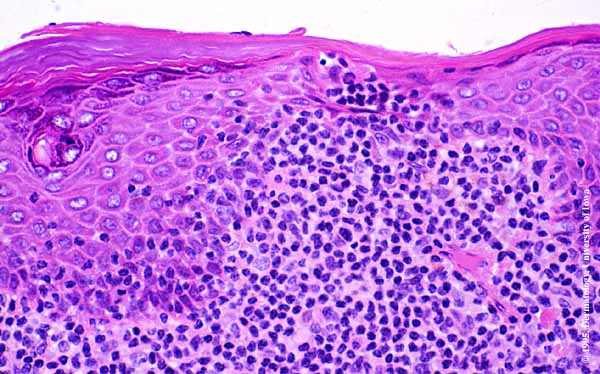

Pautrier microabscesses in Mycosis Fungoides = الخراجات المجهرية لبوترييه في التفطر الكمئي